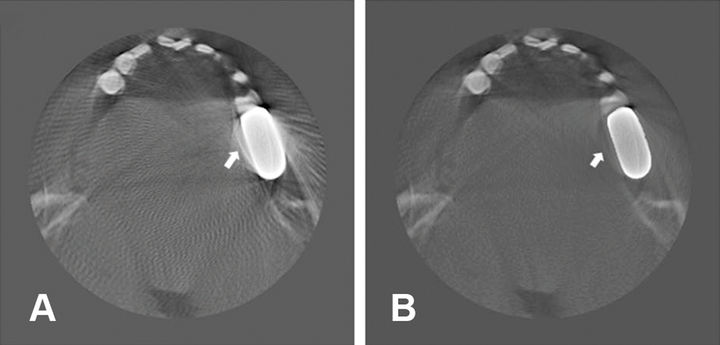

두번째로 저선량 CT의 노이즈 감소, 금속 아티팩트 개선, 해상도 증강을 통해 치과 영상의 이미지 품질을 향상시킨 알고리즘에 대한 논문들이 발표되고 있다. 저선량 CT의 경우 저에너지 X선 입자가 산란되면서 노이즈가 생기고 흐릿해지는 단점이 있는데, 이 저선량 CT에 다수의 일반 선량 CT 이미지를 학습한 알고리즘을 적용하면 노이즈를 제거한 영상을 얻을 수 있다. 결과적으로 낮은 노출선량으로 환자에게 미치는 부담을 줄이면서도 일반 선량 CT와 비슷한 품질의 3차원적 이미지를 치료에 활용할 수 있는 것이다. 이와 유사하게 금속 충전물 또는 보철물 등을 가지고 있는 환자의 경우 CT 촬영 시 발생하는 아티팩트를 보정하는 알고리즘 또한 발표된 바 있다.

한편 요즘 스마트 TV에 도입되는 해상도 증강(super-resolution) 알고리즘은 낮은 해상도의 영상을 화질저하 없이 고해상도의 영상으로 변환해준다. 이를 응용하여 기존 CBCT의 해상도를 실험 목적으로 사용되는 고선량의 micro CT의 해상도 수준으로 높임으로써 근관계 내부 공간에 대한 이미지의 정확도를 향상시킨 사례도 발표되었다. 요약컨대, 저선량 CT에서 발생하는 노이즈나 금속 보철물이 있는 환자의 CT 이미지의 아티팩트를 개선하고 더 나아가, 근관계를 관찰할 수 있을 정도의 고해상도의 이미지 또한 활용하는데 도움을 줄 것으로 전망된다.